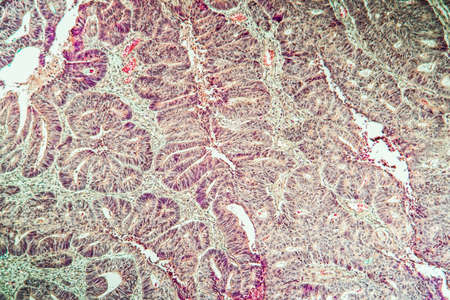

Colon carcinoma arising from adenoma, 100x